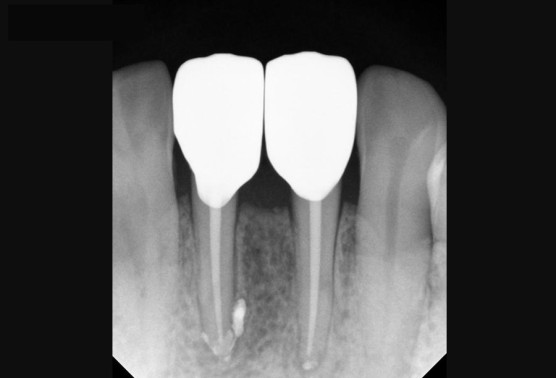

[2년 뒤 건강한 모습 (2022.01.13)]

기존의 염증은 온데간데 없이 사라졌고, 그 자리에는 뼈가 꽉 차있네요.

보철물도 기존 브릿지 타입에서 개별로 이쁘게 잘씌워 잇몸관리에도 더 좋아진 모습입니다.